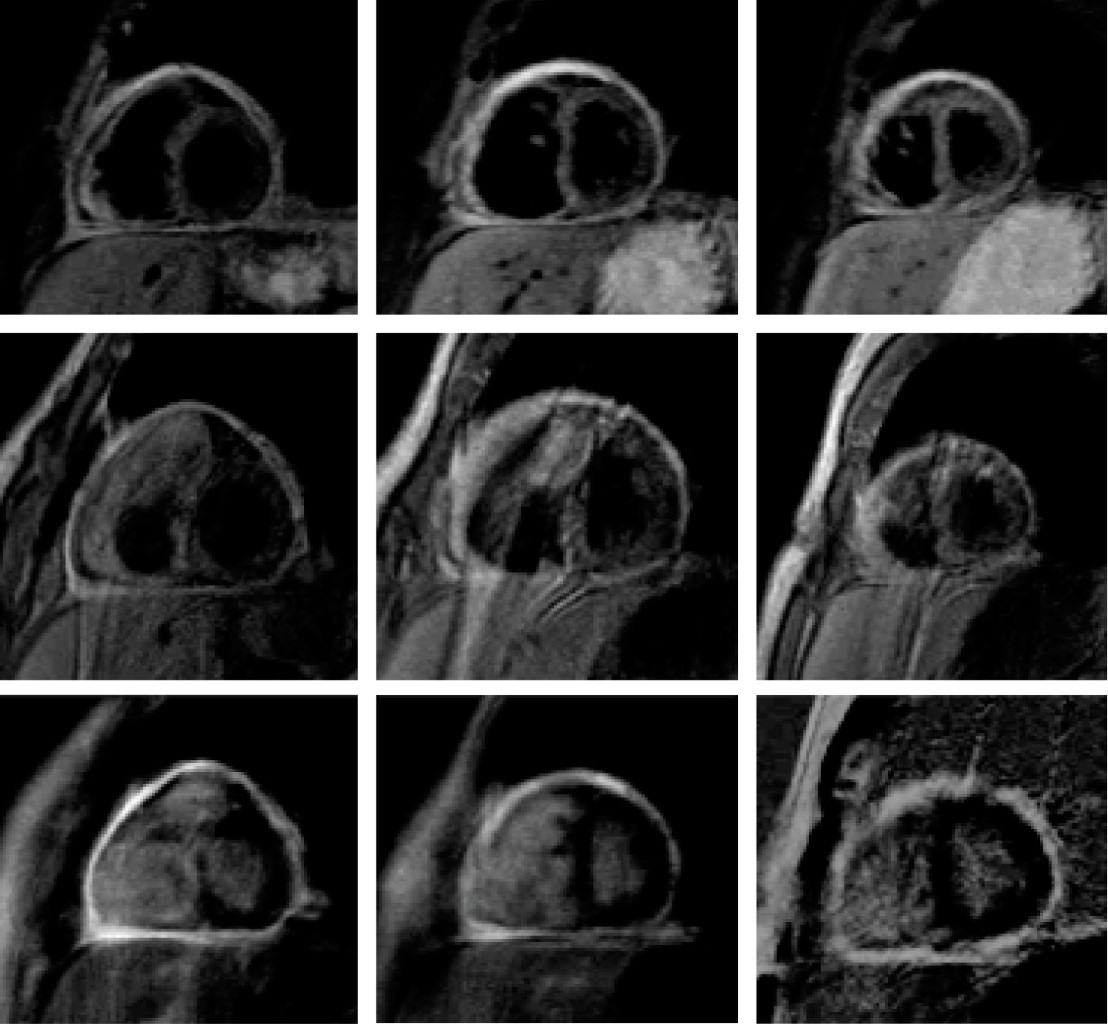

Tras emitir los diagnósticos de insuficiencia cardiaca y derrame pleural bilateral a causa de probable miocarditis, se efectuó resonancia magnética cardiaca usando resonador Philips Achieva de 1.5 teslas portando antena cardiaca en fase de 32 canales, encontrando en proyección cuatro cámaras: ventrículo izquierdo con hipertrofia anteroseptal ligera, movimiento de las paredes normal en los tres tercios, excepto por el septum interventricular, que mostro? un movimiento de "rebote" protodiastólico. Sin evidencia de obstrucción al tracto de salida; no se identificaron defectos septales atriales o ventriculares; el ventrículo derecho levemente dilatado, sin hipertrofia, acusando hipocinesia de su pared lateral (Figura 1). El pericardio mostró engrosamiento desde 2.5 hasta 5.5 mm, además de edema, reforzamiento intenso con gadolinio y escaso líquido laminar, observándose edema y reforzamiento de la pared libre del ventrículo derecho (Figura 2). Se confirma diagnóstico de miopericarditis, acompañada de disfunción ventricular derecha leve debido a fracción de expulsión del ventrículo derecho de 45%; hipertrofia anteroseptal del ventrículo izquierdo revelando función sistólica preservada (61%) y derrame pleural bilateral de predominio izquierdo.

Figura 1

Figura 2